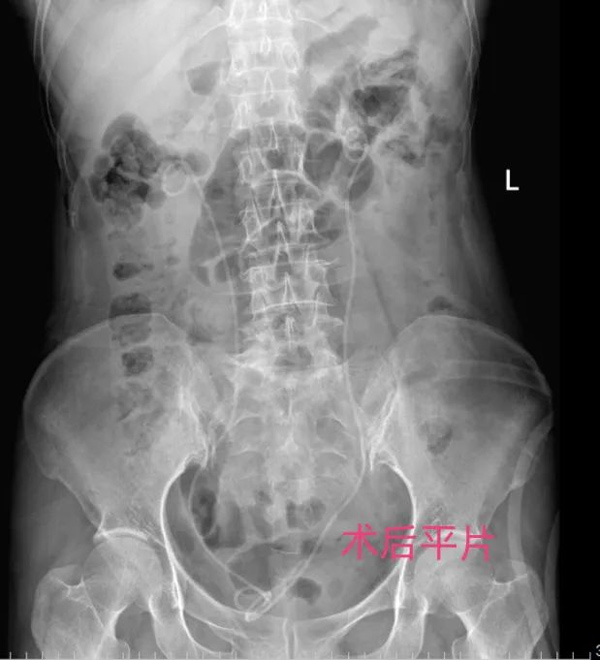

術后給予ERAS管理模式,第1天王女士就已經可下床活動并進食、進水。術后恢復理想。